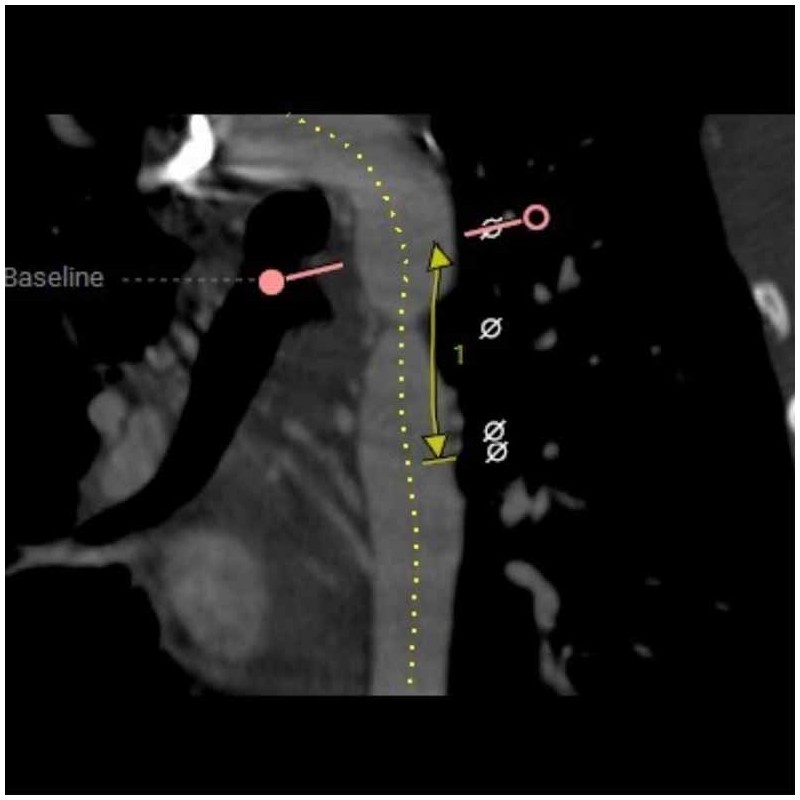

Schéma d'un stent sur une paroi d'aorte abdominale pour soigner un... Download Scientific Diagram . L'anévrisme de l'aorte abdominale est une dilatation anormale de l'aorte dans sa portion abdominale, qui peut entraîner des complications graves, notamment la rupture. L'Équipe de Rédaction est composée de rédacteurs indépendants sélectionnés pour leur capacité à communiquer des informations complexes de manière claire et utile.